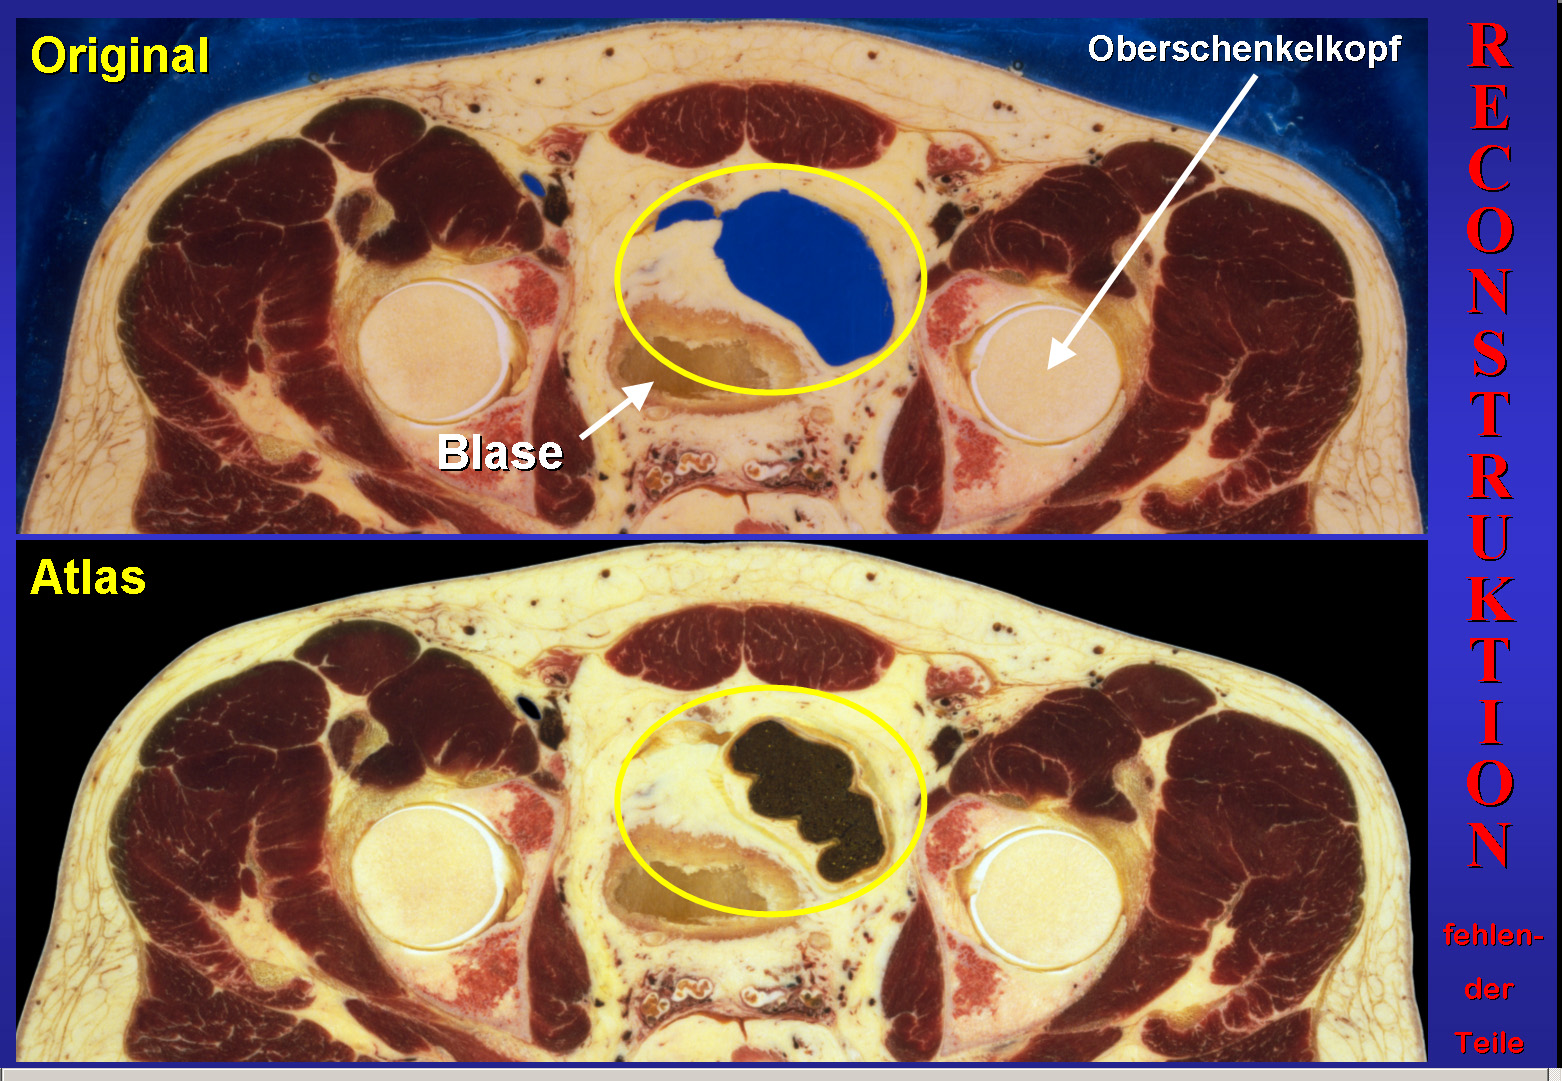

Am Beispiel des Beckens zeige ich Ihnen die Rekonstruktion größerer zerstörter Schnitteile (Abb.12). Wir betrachten nun die markierte Region.

Abb.12

Abb.13

Zunächst wurde der Hintergrund von den benachbarten Schnitten kopiert, wo er erhalten war. Dann wurden die fehlenden Anschnitte des Darms mit umgebendem Fett entlang der Ränder kopiert. Dies geschah in kleinen Schritten, denn die Quelle war größer als das zu füllende Areal. Dabei wurde auch die Stärke von Veränderungen auf vorangehenden Schnitten berücksichtigt (Abb.13).

Die Liste in Abb.14 zeigt, welche Teile der Originaldaten rekonstruiert wurden, um einen tatsächlich vollständigen Atlas zu erhalten. Natürlich kann auch die sorgfältigste Rekonstruktion nicht das exakt wiederherstellen, was beim Schneiden zerstört wurde.